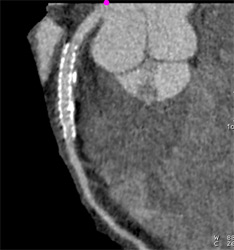

Patent Stent in LAD